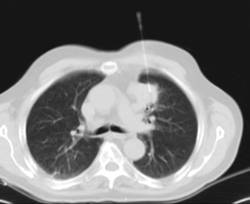

- Tórax- TC Tórax Prueba diagnóstica que consiste en obtener imágenes del tórax de alta definición anatómica (pulmones, corazón, mediastino, grandes vasos, caja torácica, etc.) mediante el empleo de un equipo de TC (Tomografía Computarizada). Dichas imágenes se estudian posteriormente en una estación de trabajo que permite reconstrucciones bidimendionales en diferentes planos del espacio y también reconstrucciones 3D (volumétricas). Algunos estudios requieren el empleo de contraste yodado para mejorar la definición de las imágenes. Prueba diagnóstica que consiste en obtener imágenes del tórax de alta definición anatómica (pulmones, corazón, mediastino, grandes vasos, caja torácica, etc.) mediante el empleo de un equipo de TC (Tomografía Computarizada). Dichas imágenes se estudian posteriormente en una estación de trabajo que permite reconstrucciones bidimendionales en diferentes planos del espacio y también reconstrucciones 3D (volumétricas). Algunos estudios requieren el empleo de contraste yodado para mejorar la definición de las imágenes.

- Angio-TC Arterias pulmonares (Estudio TEP, Tromboembolismo Pulmonar) Prueba diagnóstica que consiste en el estudio de las arterias pulmonares mediante el empleo de un equipo de TC (Tomografía Computarizada) obteniendo imágenes bi y tridimensionales. En este estudio es imprescindible el uso de contraste yodado, el cual permitirá una mejor definición anatómica. Esta prueba está principalmente indicada en los casos de sospecha de tromboembolismo pulmonar (TEP) para descartar o confirmar la presencia de coágulos sanguíneos en el interior de las arterias. Prueba diagnóstica que consiste en el estudio de las arterias pulmonares mediante el empleo de un equipo de TC (Tomografía Computarizada) obteniendo imágenes bi y tridimensionales. En este estudio es imprescindible el uso de contraste yodado, el cual permitirá una mejor definición anatómica. Esta prueba está principalmente indicada en los casos de sospecha de tromboembolismo pulmonar (TEP) para descartar o confirmar la presencia de coágulos sanguíneos en el interior de las arterias.